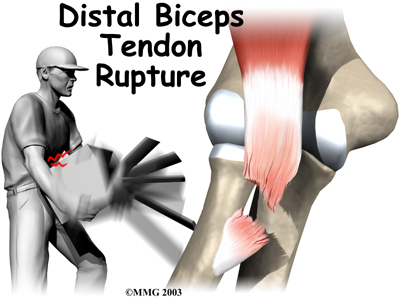

A distal biceps rupture occurs when the tendon attaching the biceps muscle to the elbow is torn from the bone. This injury occurs mainly in middle-aged men during heavy work or lifting. A distal biceps rupture is rare compared to ruptures where the top of the biceps connects at the shoulder. Distal biceps ruptures make up only three percent of all biceps tendon ruptures.

The most common cause of a distal biceps rupture happens when a middle-aged man lifts a box or other heavy item with his elbows bent. Often the load is heavier than expected, or the load may shift unexpectedly during the lift. This forces the elbow to straighten, even though the biceps muscle is working hard to keep the elbow bent. The biceps muscle contracts extra hard to help handle the load. As tension on the muscle and tendon increases, the distal biceps tendon where it connects to the radius.

When the distal biceps tendon ruptures, it usually sounds and feels like a pop directly in front of the elbow. At first the pain is intense. The pain often subsides quickly after a complete rupture because tension is immediately taken off the pain sensors in the tendon. Swelling and bruising in front of the elbow usually develop shortly after the pop. The biceps may appear to have balled up near the elbow. The arm often feels weak with attempts to bend the elbow, lift the shoulder, or twist the forearm into supination (palm up).